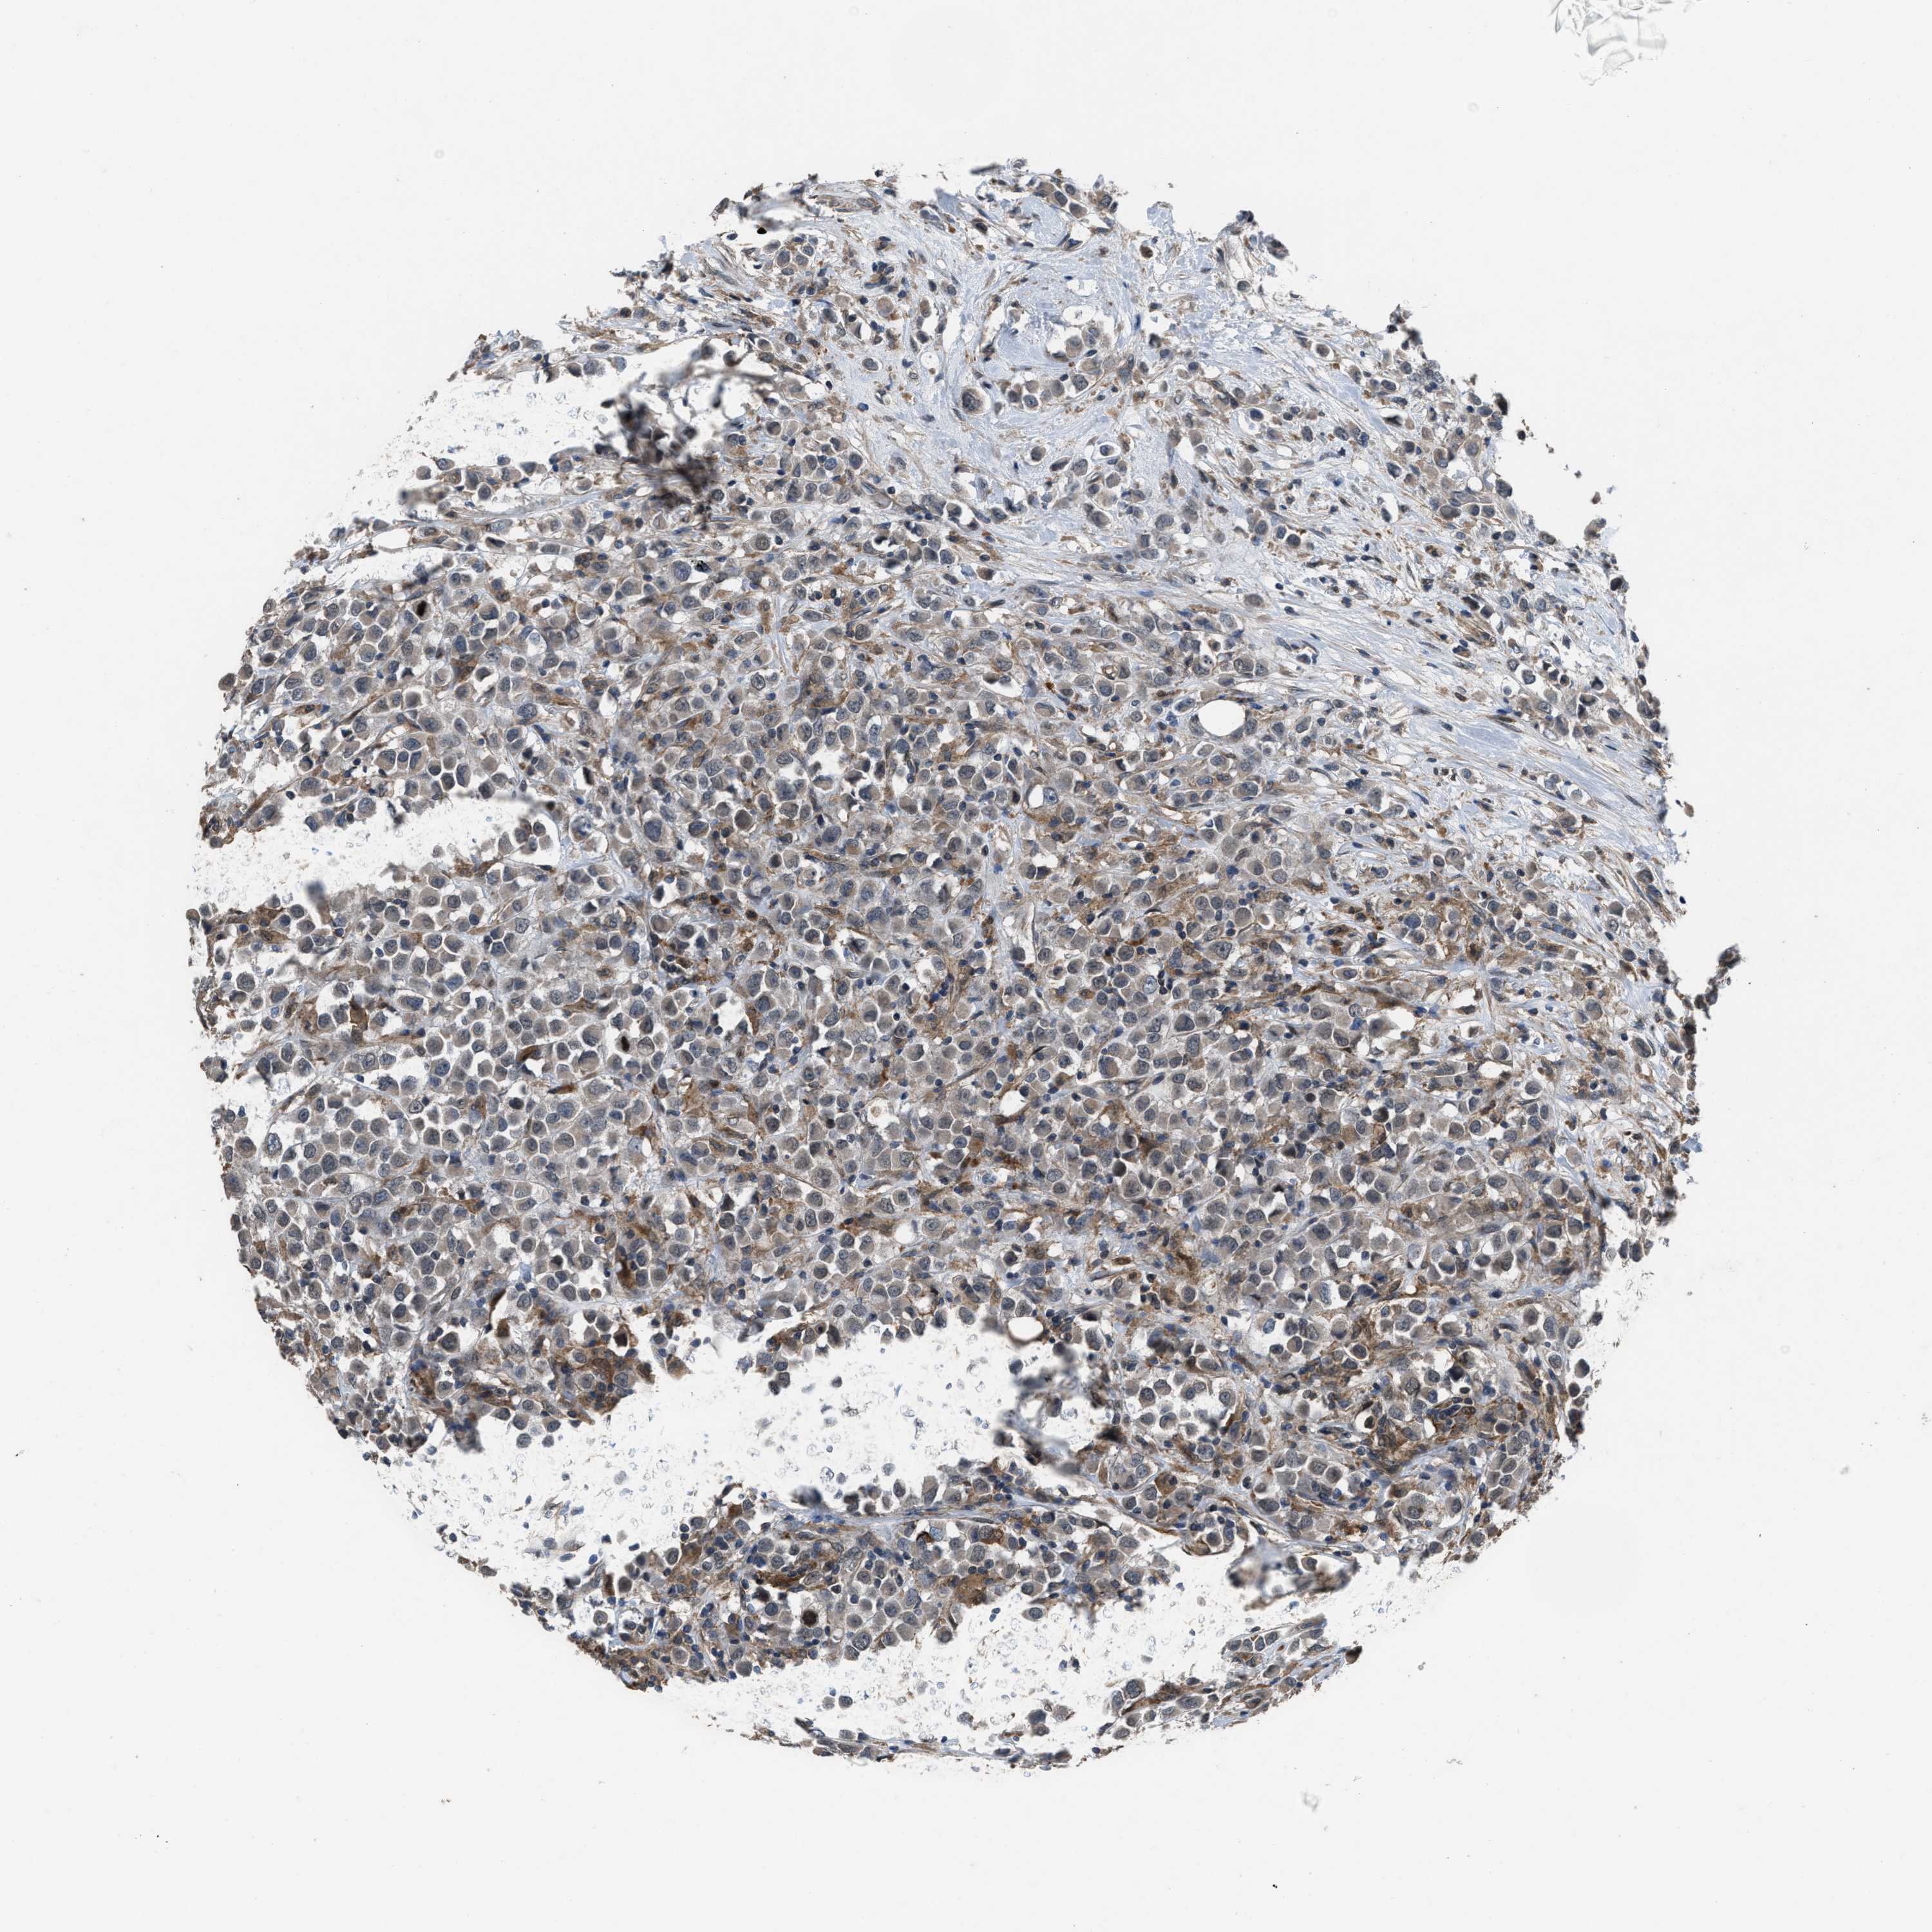

CANCER BREAST CANCER Show tissue menu

BRCA TCGA BRCA VALIDATION PROTEIN EXPRESSION